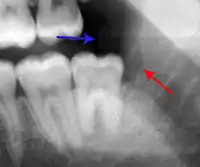

Clinical & xray correlation of pericoronitis

An operculum (green arrow) over a partially erupted lower left third molar tooth. There is minimal inflammation and recurrent swelling.

xray of pericoronitis

A radiograph of the above tooth showing chronic pericoronitis, operculum (blue arrow) and bone destruction (red arrow) from chronic inflammation. Tooth is slightly disto-angular.

Pericoronitis is inflammation of the soft tissues surrounding the crown of a partially erupted tooth.[25] The lower wisdom tooth is the last tooth to erupt into the mouth, and is, therefore, more frequently impacted, or stuck, against the other teeth. This leaves the tooth partially erupted into the mouth, and there frequently is a flap of gum (an operculum), overlying the tooth. Bacteria and food debris accumulate beneath the operculum, which is an area that is difficult to keep clean because it is hidden and far back in the mouth. The opposing upper wisdom tooth also tends to have sharp cusps and over-erupt because it has no opposing tooth to bite into, and instead traumatizes the operculum further. Periodontitis and dental caries may develop on either the third or second molars, and chronic inflammation develops in the soft tissues. Chronic pericoronitis may not cause any pain, but an acute pericoronitis episode is often associated with pericoronal abscess formation. Typical signs and symptoms of a pericoronal abscess include severe, throbbing pain, which may radiate to adjacent areas in the head and neck,[21][26]:122 redness, swelling and tenderness of the gum over the tooth.[27]:220–222 There may be trismus (difficulty opening the mouth),[27]:220–222 facial swelling, and rubor (flushing) of the cheek that overlies the angle of the jaw.[21][26]:122 Persons typically develop pericoronitis in their late teens and early 20s,[28]:6 as this is the age that the wisdom teeth are erupting. Treatment for acute conditions includes cleaning the area under the operculum with an antiseptic solution, painkillers, and antibiotics if indicated. After the acute episode has been controlled, the definitive treatment is usually by tooth extraction or, less commonly, the soft tissue is removed (operculectomy). If the tooth is kept, good oral hygiene is required to keep the area free of debris to prevent recurrence of the infection.[21]:440–441